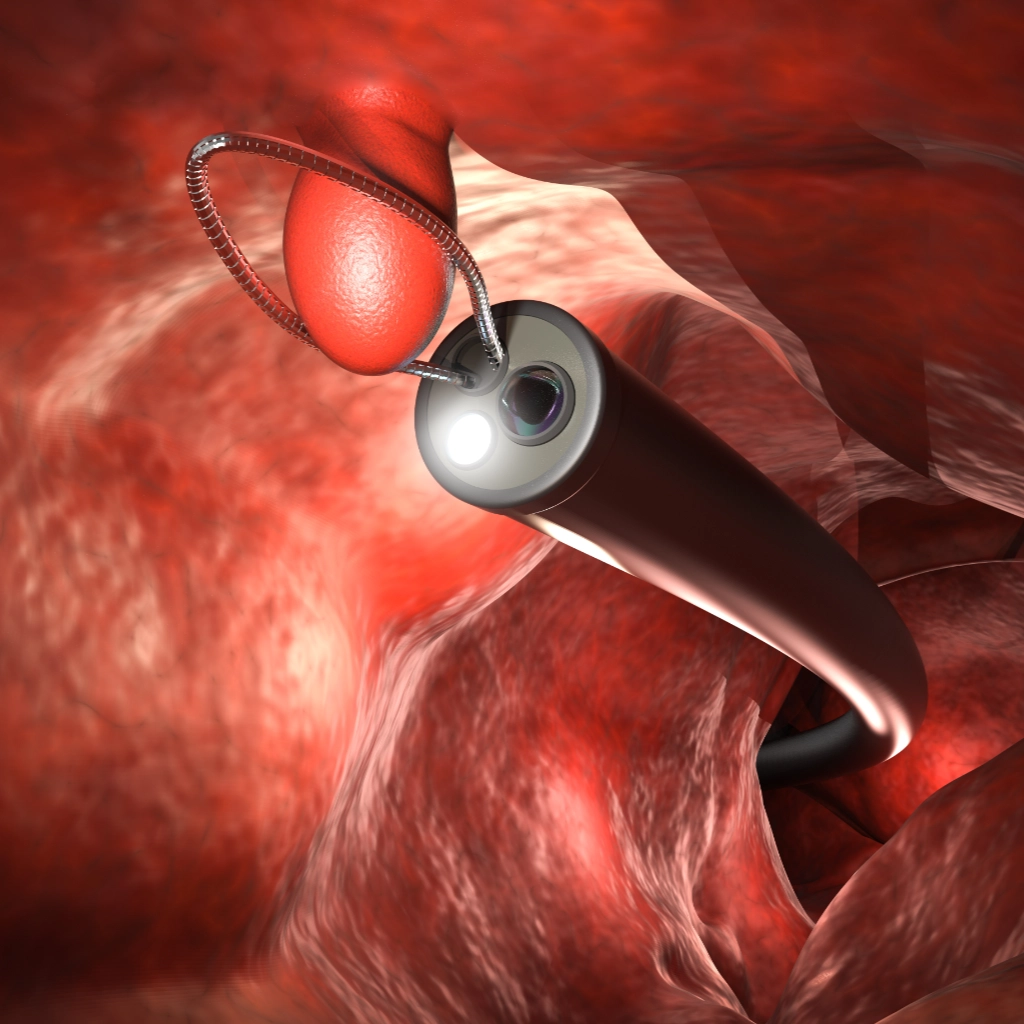

内視鏡治療は、消化管の粘膜にできた早期がんや前がん病変を、体表に傷をつけずに切除する低侵襲治療です。代表的な方法に、EMR(内視鏡的粘膜切除術)ESD(内視鏡的粘膜下層剥離術)があります。

病変の大きさや位置、深達度などに応じて適切な術式を選択します。多くは日帰りまたは短期入院で実施でき、開腹手術に比べて身体への負担が少なく、回復が早いのが特長です。

当院では、安全性が確認できる病変のみを対象として、早期胃がんに対するESD(内視鏡的粘膜下層剥離術)を実施しています。特殊な電気メスを用いて病変の下の層(粘膜下層)を丁寧に剥がします。

EMRはスネアを用いて病変を絞扼後、高周波装置を用いて通電切除を行う切除方法です。がんもEMRで治療することができ、比較的安全な処置が可能であり、良好な治療成績が得られています。当院で実施した大腸EMRの実際は以下の通りです。